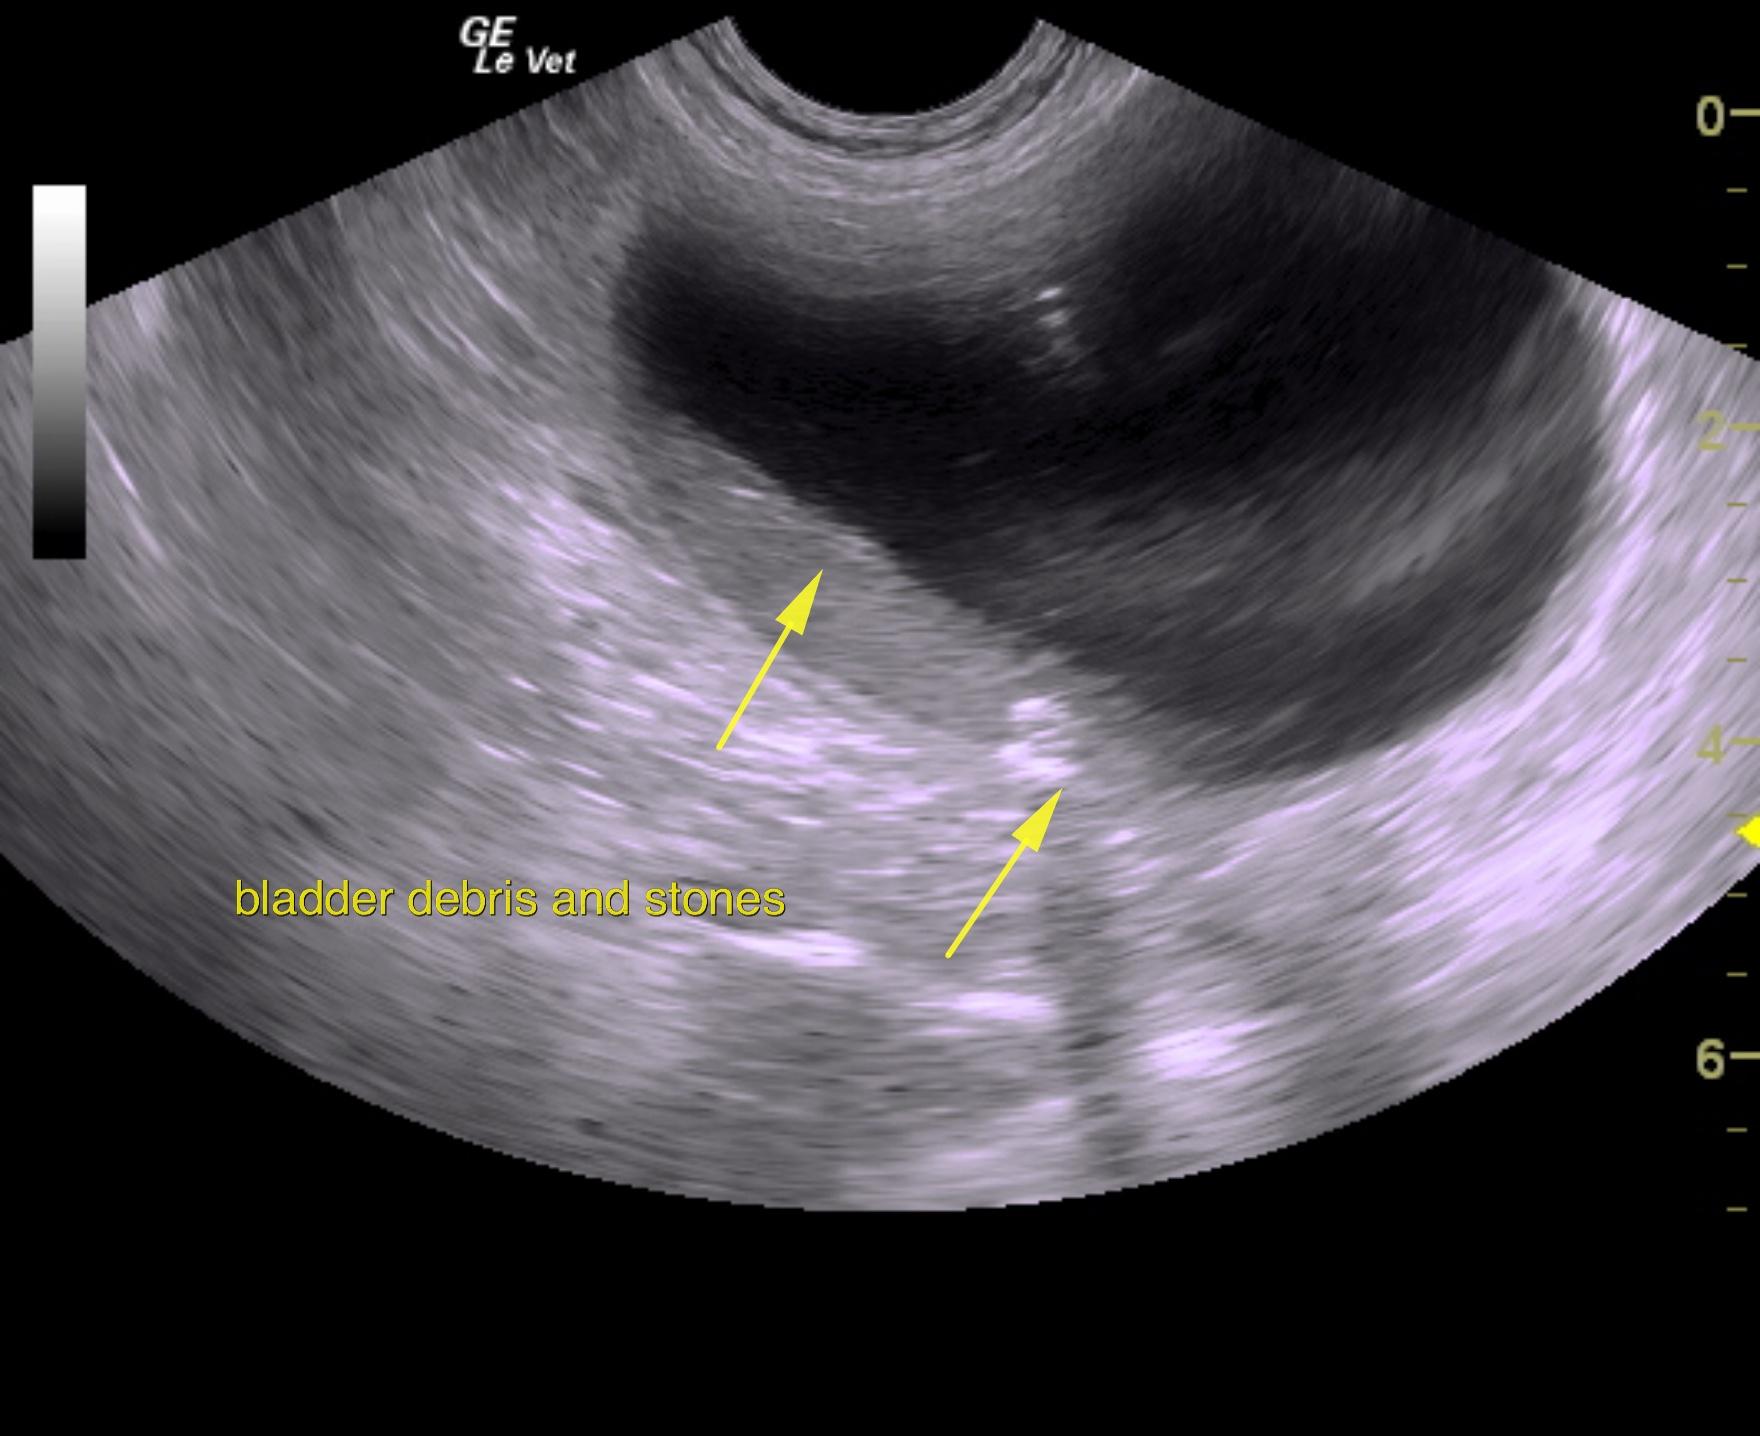

A 5-years-old male neutered Shih Tzu was presented for evaluation of urethral obstruction that had been managed with catheterization. Urinalysis showed SG of 1.008 and proteinuria. Abnormalities on CBC and serum biochemistry were neutrophilia and monocytosis, elevated phosphorus, and azotemia; the latter had improved after being catheterized.